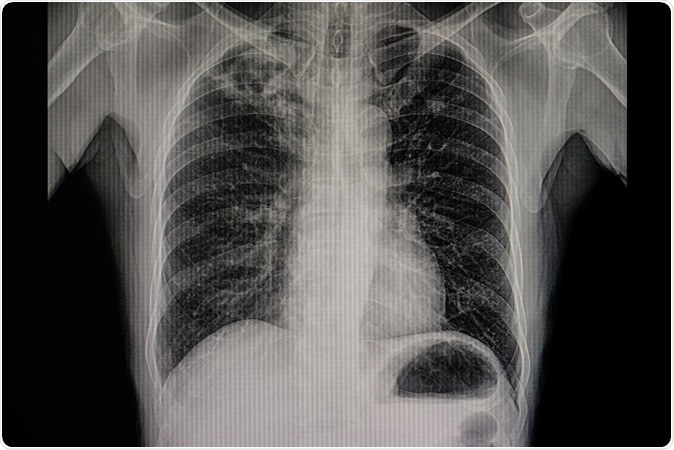

Xray film of a patient with active pulmonary tuberculosis with numerous cavitations and fibrotic change in the right upper lung. Infectious and contagious disease. TB communicable respiratory disease. Image Credit: Tomatheart / Shutterstock

Xray film of a patient with active pulmonary tuberculosis with numerous cavitations and fibrotic change in the right upper lung.  Image Credit: Tomatheart / Shutterstock